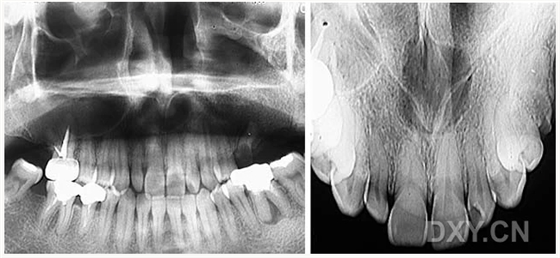

鼻竇炎(注意不要誤診呀)

良性成牙骨質(zhì)細(xì)胞瘤